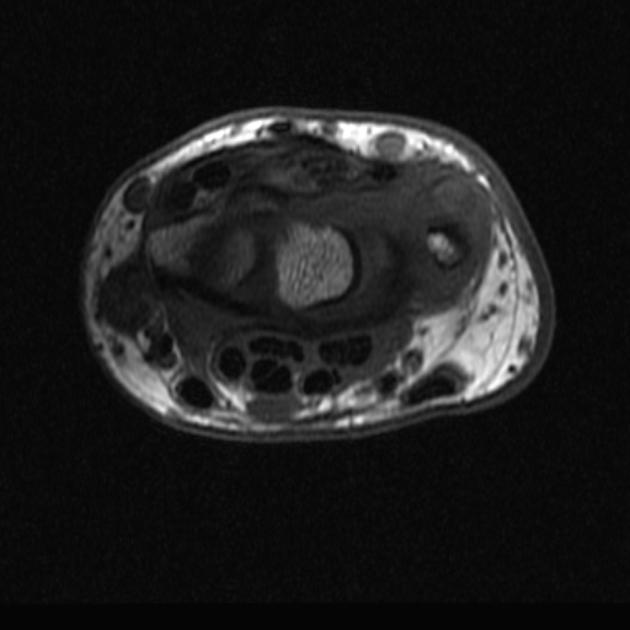

2. Tenosynovitis on MRI: Types & Tricks with Dr. Gursimran Singh Anand

MRI can be overwhelming—but not with this video. Decode the full spectrum of tenosynovitis with beautiful MRI examples.

• Role of T1, T2, STIR, GRE, and contrast

• Red flags like rice bodies, synovial thickening, PVNS

• How to distinguish inflammatory, infectious, and neoplastic causes